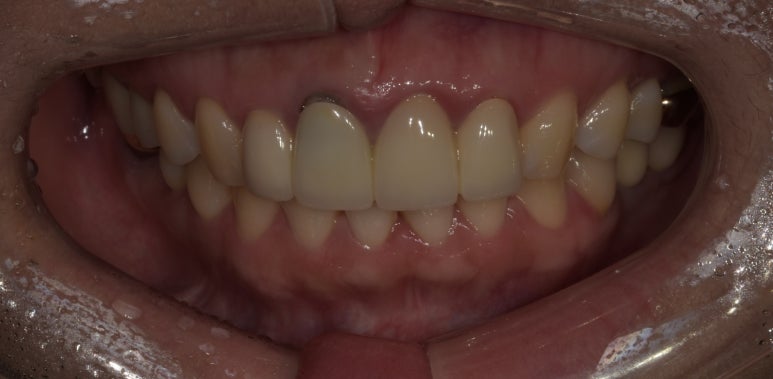

앞니브릿지교체

2023-05-15

치아와 잇몸의 변색이 있던 부분도 말끔하게 사라졌고, 다른 치아 역시도 자연스럽게 완성된 모습을 확인하실 수 있습니다.

전에는 치아 사이즈가 다소 길었는데, 이번에는 약간 짧게 제작해 더 영해보일 수 있도록 했습니다.

앞으로 향후 10년 이상 문제없이 쓰실 수 있도록 스케일링과 잇몸치료도 꾸준히 받으시면서 잘 관리하실 것을 당부드렸습니다.